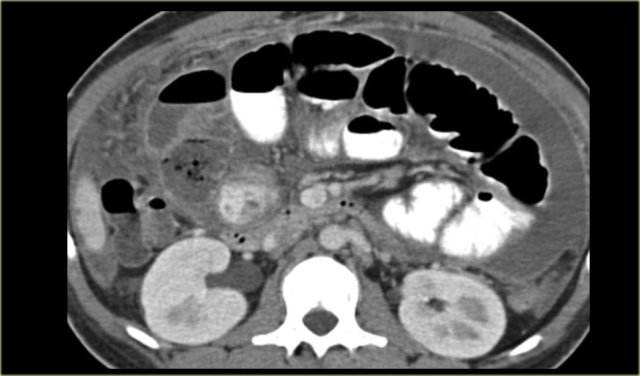

Echinococcal Cyst

It is unusual for an echinococcal cyst to be located in the peritoneum.

It favors the liver, the spleen and even the kidney over the peritoneum.

On the left we see cysts in the peritoneum and in the spleen.

Notice the daughter cysts as small dark lesions within the large peritoneal cyst (arrows).

In the pelvis additional echinococcal cysts are seen.